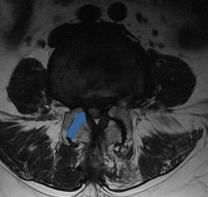

• 脊柱内镜侧后路联合减压术治疗腰神经根双卡综合征的临床疗效观察

2025, 31(12):25-32. DOI: 10.12235/E20250012

摘要 (122) HTML (46) PDF 10.14 M (90) 评论 (0) 收藏

摘要:目的 观察脊柱内镜侧后路联合减压术治疗腰神经根双卡综合征(DCS)的临床疗效、可行性、安全性和有效性。方法 回顾性分析2018年9月-2023年9月于该院就诊的50例腰椎退行性病变致腰神经根DCS患者的临床资料,根据手术方法不同,将患者分为观察组(37例)和对照组(13例)。观察组行脊柱内镜侧后路联合减压术治疗,对照组行非手术治疗。比较两组患者治疗前、治疗后1周、治疗后3个月、治疗后6个月和治疗后12个月的疼痛视觉模拟评分法(VAS)评分、Oswestry功能障碍指数(ODI)和日本骨科协会(JOA)评分。末次随访时,采用改良Macnab标准,评估临床疗效;采用腰椎MRI检查,评估椎间隙高度和椎间盘退变改良Pfirrmann分级。比较两组患者治疗的安全性(包括:并发症发生情况、复发情况和转手术治疗情况)。结果 50例患者均顺利完成治疗。两组患者术后VAS评分和ODI呈下降趋势,JOA评分呈升高趋势,观察组术后各时点VAS评分和ODI明显低于术前,且明显低于对照组,术后各时点JOA评分明显高于术前,且明显高于对照组,差异均有统计学意义(P < 0.05);观察组优良率为86.49%,明显高于对照组的76.92%,差异有统计学意义(P < 0.05);两组患者末次随访时,椎间隙高度和椎间盘退变Pfirrmann分级比较,差异均无统计学意义(P > 0.05)。两组患者围手术期均未出现神经损伤和脑脊液漏等严重并发症,观察组术后1例出现下肢放射性疼痛;观察组1例术后3个月出现腰椎间盘再突出;对照组有3例转手术治疗。结论 与非手术治疗相比,脊柱内镜侧后路联合减压术可更为安全、有效地缓解腰神经根DCS患者的疼痛,改善下肢功能,且早、中期临床疗效好。值得临床推广应用。